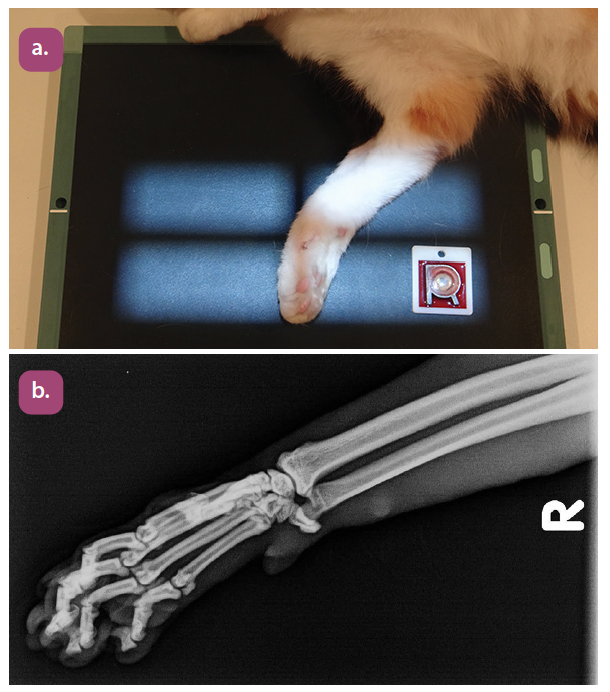

dorsopalmar projection of the carpus

dorsopalmar projection of the metacarpus

mediolateral projection of the metacarpus